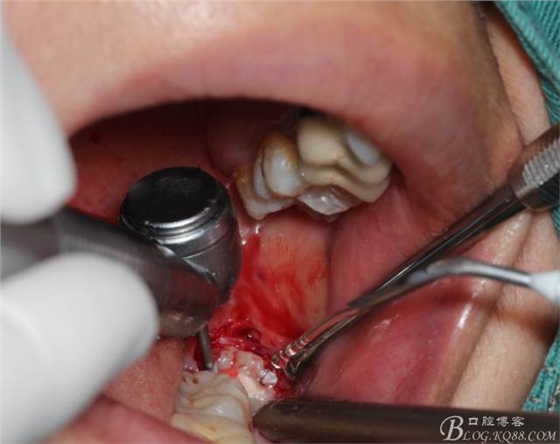

切開:角形切口,這個位置切開我喜歡更易操作12#刀。

鈍性翻辨露冠

角度鍋輪機結(jié)合冷鹽水冷卻分冠